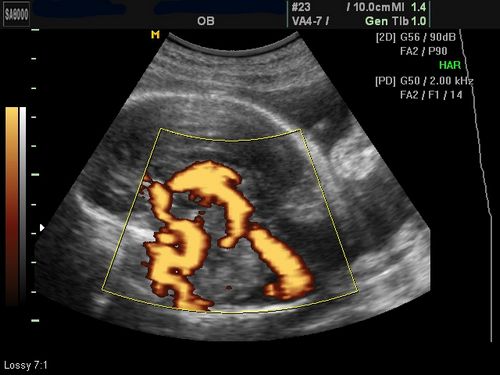

• Планове УЗД. якщо воно не було зроблено тижнем раніше. На цьому УЗД лікарі роблять прогнози щодо того, як пройдуть пологи, встановлюються показання для кесаревого розтину (якщо вони є). Перевіряється відповідність розмірів плода терміну вагітності, стан внутрішніх органів, передлежання плода. Також досліджується стан плаценти і ступінь її зрілості, стан шийки матки і навколоплідних вод, виявляється обвиття плоду пуповиною.

УЗД на 32 тижні вагітності (фото)